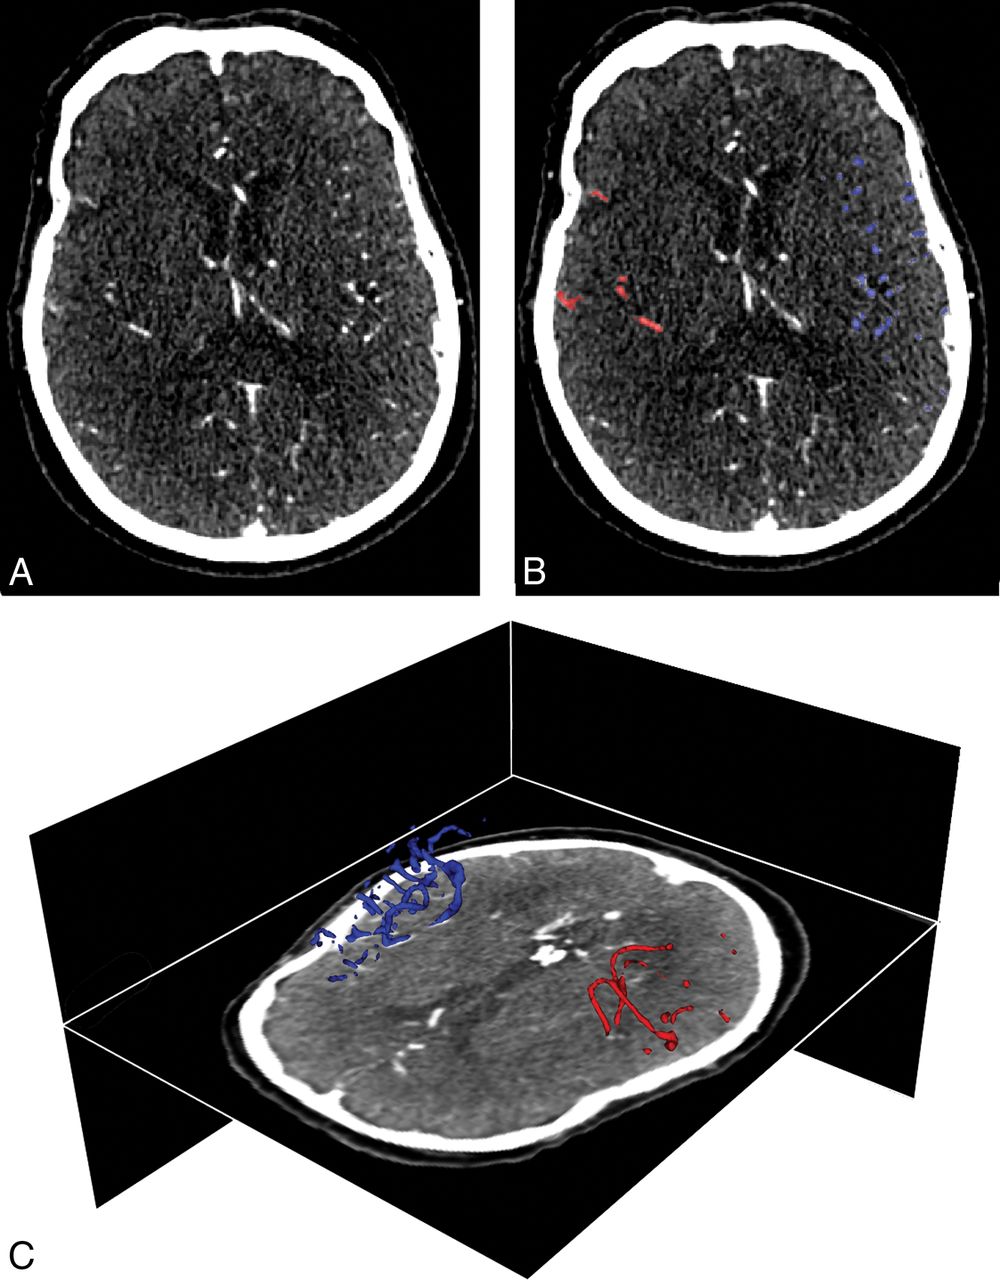

The imaging committee of MR CLEAN assessed the visual collateral score (vCS) using the method of Tan et al.18 All observers had >10 years of experience and were blinded to all clinical findings except the symptom side. Two neuroradiologists independently graded all CTA images. A third reader resolved any discrepancies. In the 4-point vCS scale, a score of zero indicated absent collaterals (0% filling of the occluded territory), 1 indicated poor collaterals (>0% and ≤50% filling of the occluded territory), 2 indicated moderate collaterals (>50% and <100% filling of the occluded territory), and 3 indicated good collaterals (100% filling of the occluded territory).18 A mixture of the CTA source images and maximum-intensity-projections was used for visual assessment. If different slices expressed different filling, an average collateral score over all available slices was determined. Agreement beyond chance with a κ of 0.60 has previously been reported in MR CLEAN.9 An example of qCS scoring is shown in Fig 1.

An example of quantitative collateral capacity scoring. A, An axial plane of a baseline CTA image acquired in the peak venous phase with a right-sided M1 segment occlusion of the MCA territory. B, Segmentation results of automated quantitative collateral assessment of the ipsilateral (red) and contralateral (blue) hemispheres. The quantitative collateral score was 46%. C, 3D representation of the segmented vasculature.